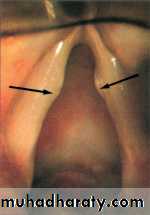

Depressing the tongue may show swollen, red cherry epiglottis but no attempt should be made to examine the larynx as this may end in fatal total obstruction. It is better done in operation theature where facilities for intubation or tracheostomy are available.

Lateral X-ray of the neck may show swollen epiglottis (thumb sign).

Steeple sign (Croup) Thumb sign (Epiglottitis)